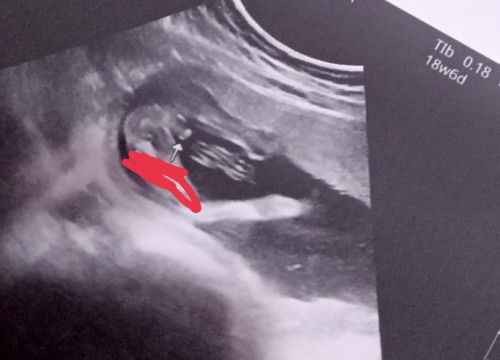

100% boy??

18w6d po si baby during this ultrasound. Sabi ng sonologist, too early to tell yung gender. Pero nilagay nya na, na boy. Will have CAS (end of month) to confirm my baby's gender. Sa tingin niyo po mga mommies?